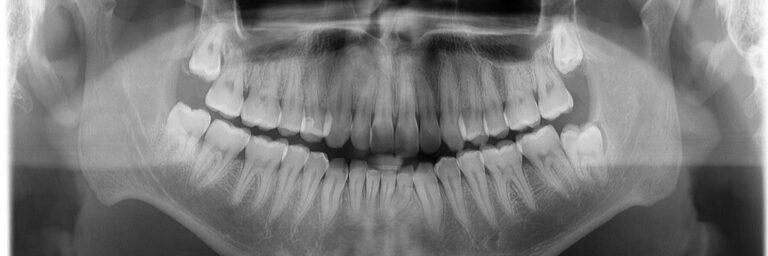

Unsere moderne Zahnarztpraxis bietet heute mehr als nur die einfache Zahnbehandlung. Viele Behandlungsmethoden und Materialien haben sich verändert. Es gibt heute mehr Möglichkeiten, Zähne zu erhalten und bei Verlust die Ästhetik wieder optimal herzustellen. Aber auch Altbewährtes hat seinen Platz in unserer täglichen Arbeit. Wir möchten Ihnen nachfolgend eine Auswahl unseres Leistungsspektrums neben der alltäglichen Kariestherapie vorstellen. Bitte zögern Sie nicht, uns bei Fragen in der Praxis anzusprechen.